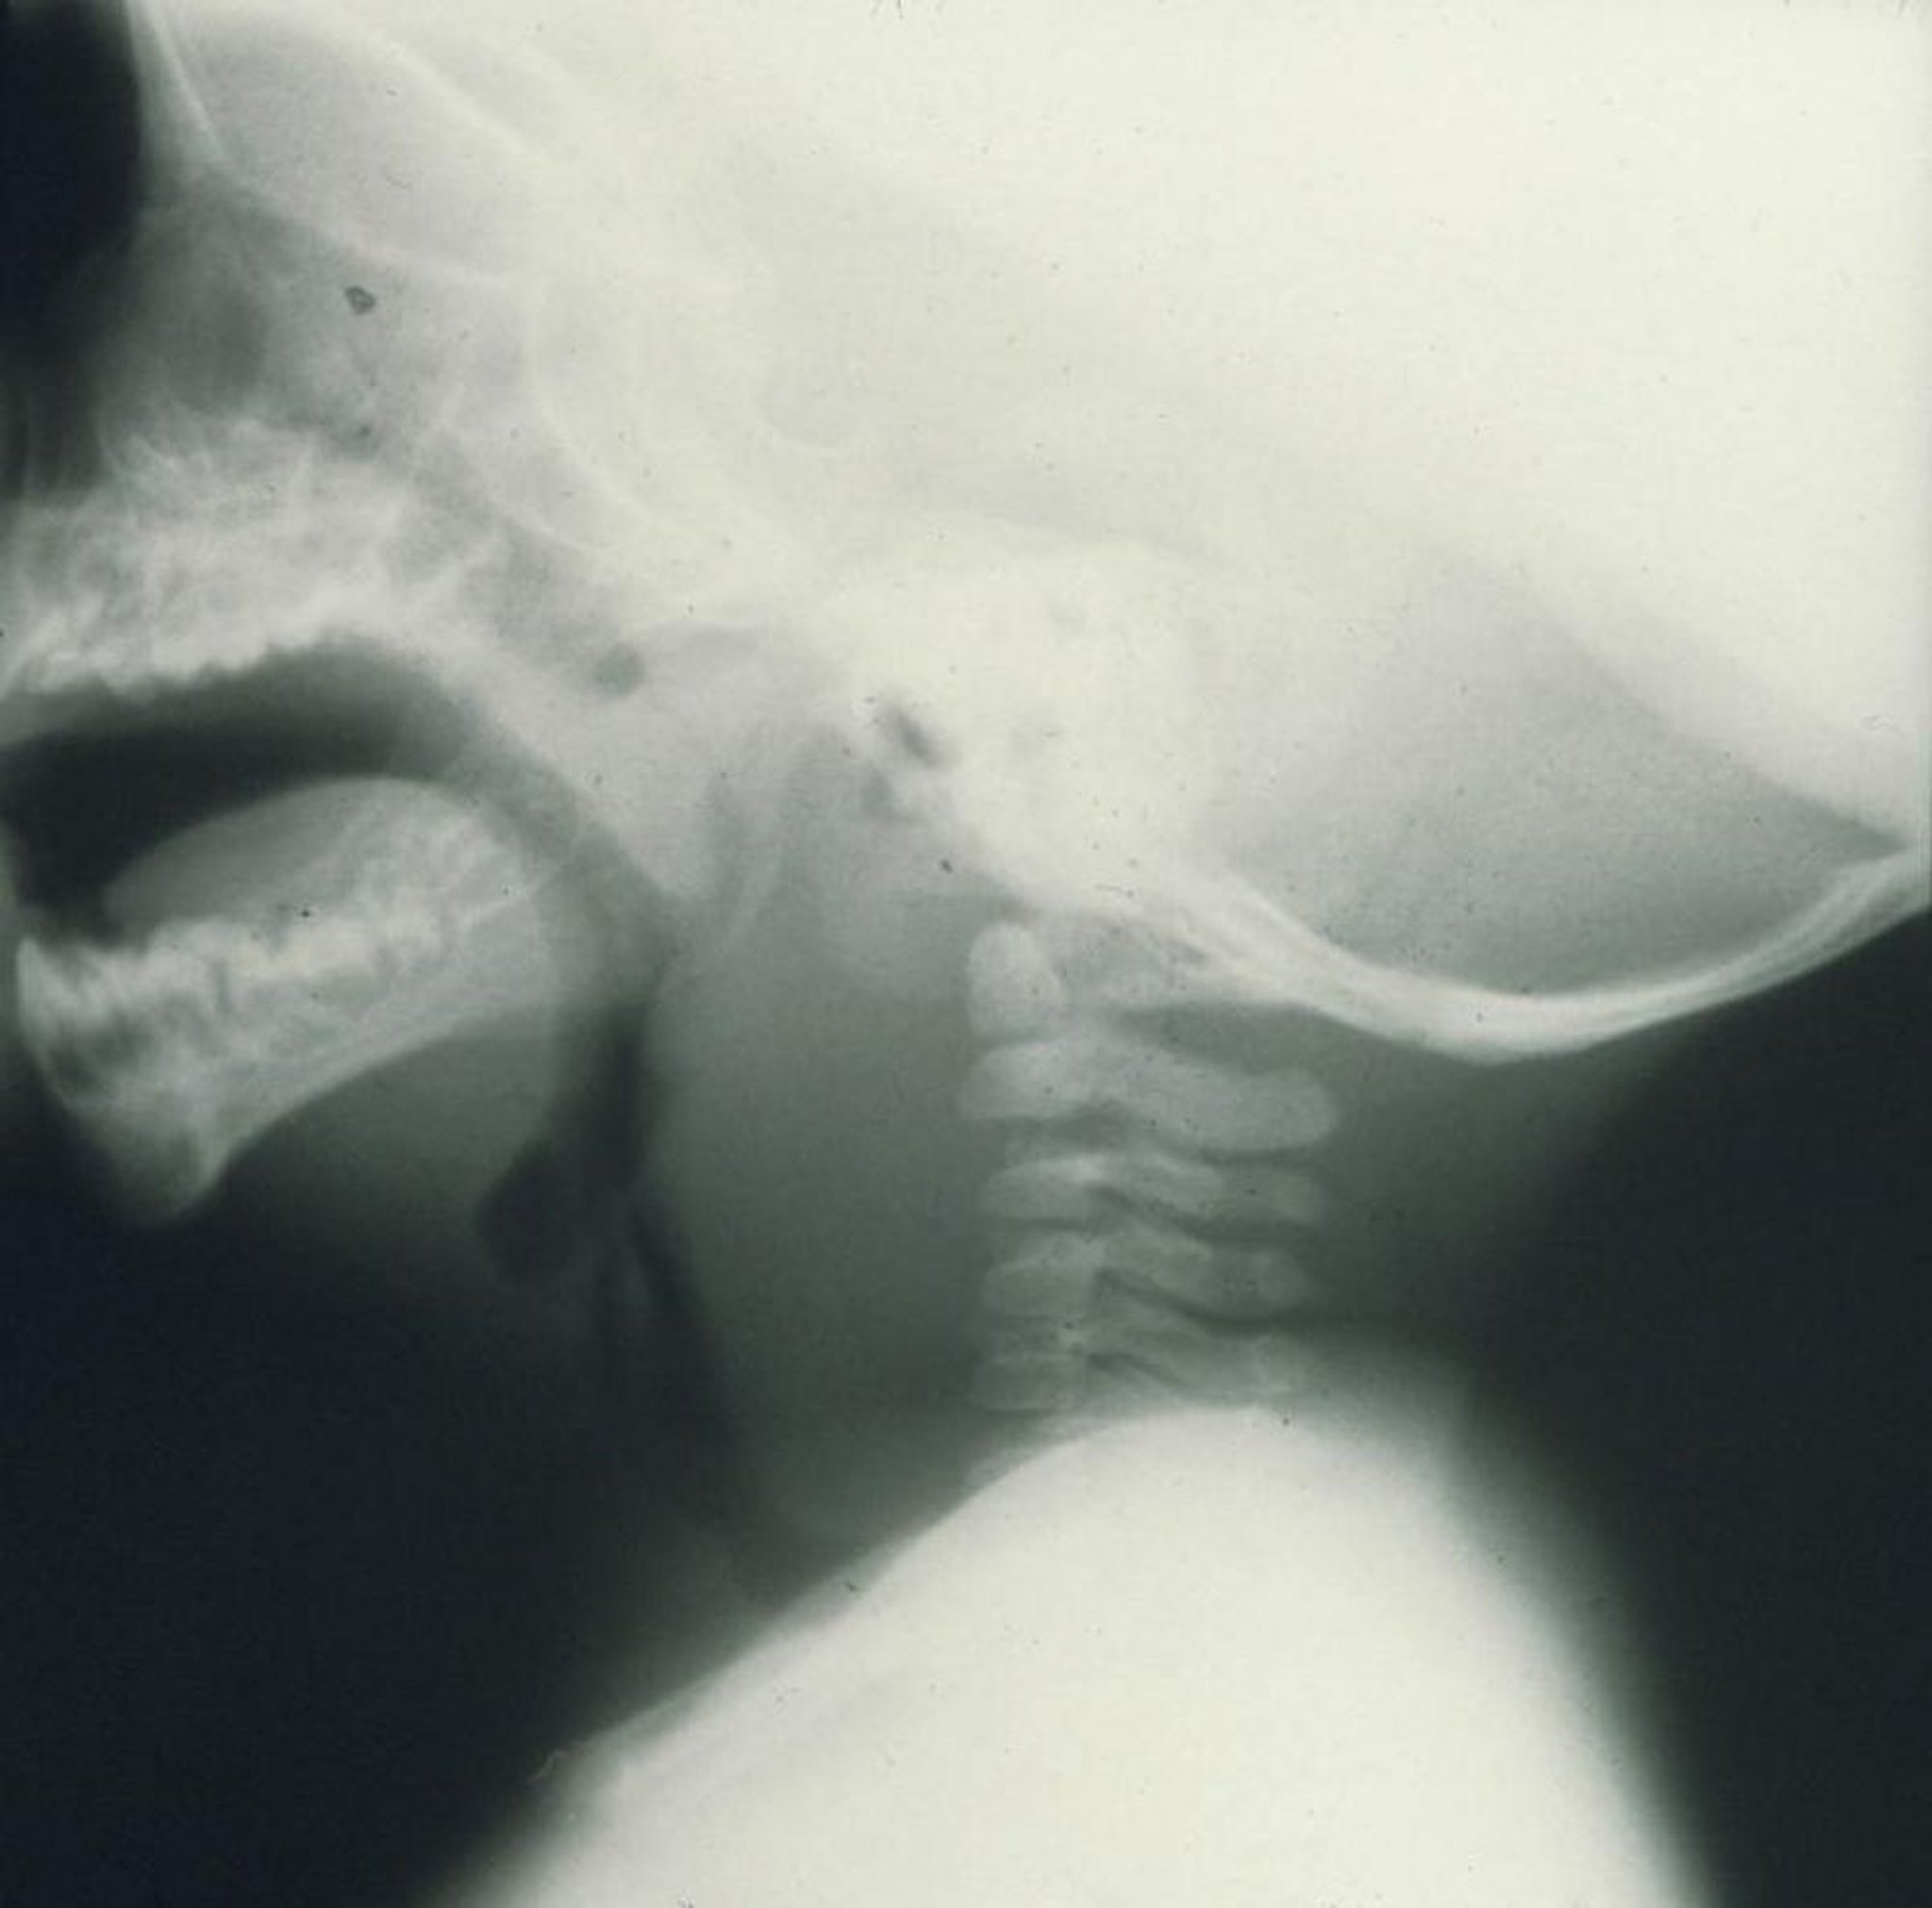

Retropharyngealabszess

Diese seitliche Röntgenaufnahme eines Kindes zeigt eine ausgeprägte Schwellung anterior der Halswirbelsäule, die durch einen retropharyngealen Abszess verursacht wird.

Image provided by Clarence T. Sasaki, MD.